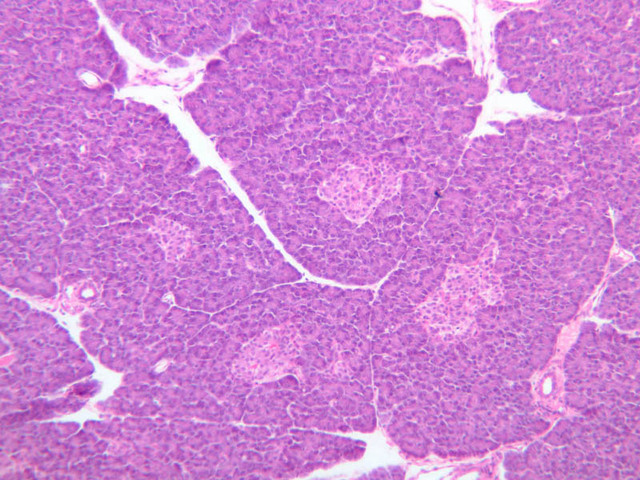

Scan slide B-36 (H&E [10x, 20x] [10x, 20x). Note that in this H&E preparation most of the pancreas consists of rather compactly arranged, darkly stained cells. The compact, darkly stained regions constitute the exocrine portion of the pancreas. (Of what organ does the exocrine pancreas remind you?) The endocrine portions of the pancreas consist of small bits, or islands, of more lightly stained tissue that is somewhat irregularly dispersed within the substance of the exocrine pancreas. Drawing on the name of their discoverer, the endocrine portions of the pancreas are known as the islets of Langerhans.

Endocrine pancreas

Although H & E staining permits ready identification of the islets of Langerhans, it does not permit differentiation of the various cell types that comprise the islets (B-36, H&E [10x, 20x, 40x-labeled]). There are no slides in the class collection that permit identification of all of the cell types of the endocrine pancreas. However, the sections on slides B-37 and B-40 permit specific identification of two cell types. Slide B-37 has been stained by the aldehyde fuchsin technique, which lends a magenta coloration to the granules of the insulin-producing B-cells. All other cells in the islets stain a dirty orange color (B-37 [10x, 20x, 40x] [10x, 20x, 40x]). Most of these orange-colored cells are the glucagon-secreting A-cells; however, you should bear in mind that somatostatin-secreting D-cells, as well as APUD cells that secrete pancreatic polypeptide are also scattered about the islet. The section on slide B-40 has been prepared by a silver impregnation method that renders some of the APUD cells in the islets (which appear as “clear cells” in ordinary preparations) dark brown or black (B-40 [10x, 20x, 40x]).